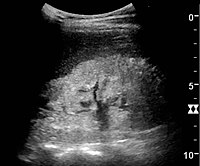

Ultrasound[edit | edit source]

Kidney ultrasonography is useful for diagnostic and prognostic purposes in chronic kidney disease. Whether the underlying pathologic change is glomerular sclerosis, tubular atrophy, interstitial fibrosis or inflammation, the result is often increased echogenicity of the cortex. The echogenicity of the kidney should be related to the echogenicity of either the liver or the spleen (Figure 22 and Figure 23). Moreover, decreased kidney size and cortical thinning are also often seen and especially when disease progresses (Figure 24 and Figure 25). However, kidney size correlates to height, and short persons tend to have small kidneys; thus, kidney size as the only parameter is not reliable.[44]